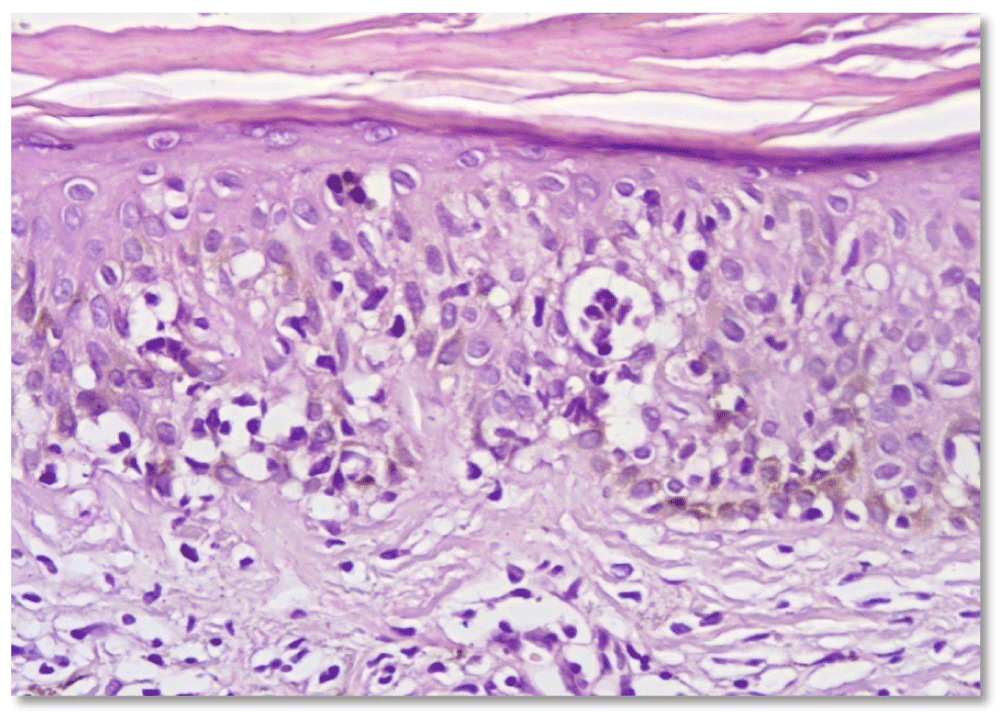

Ichthyosiform mycosis fungoides: An atypical variant of cutaneous T-cell lymphoma : About a case and literature review

Elharrouni Alaoui Aicha*, Elloudi Sara, Douhi Zakia, Baybay Hanane and Mernissi Fz

Acquired ichthyosis is a known paraneoplastic sign of lymphoproliferative malignancies, with histopathologic findings that are nonspecific, revealing no insinuation of the underlying neoplasm.